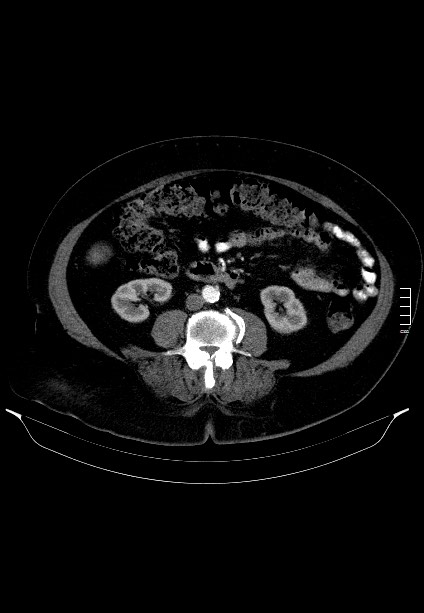

2909. КТ-Исследование выполнено в _____ фазу